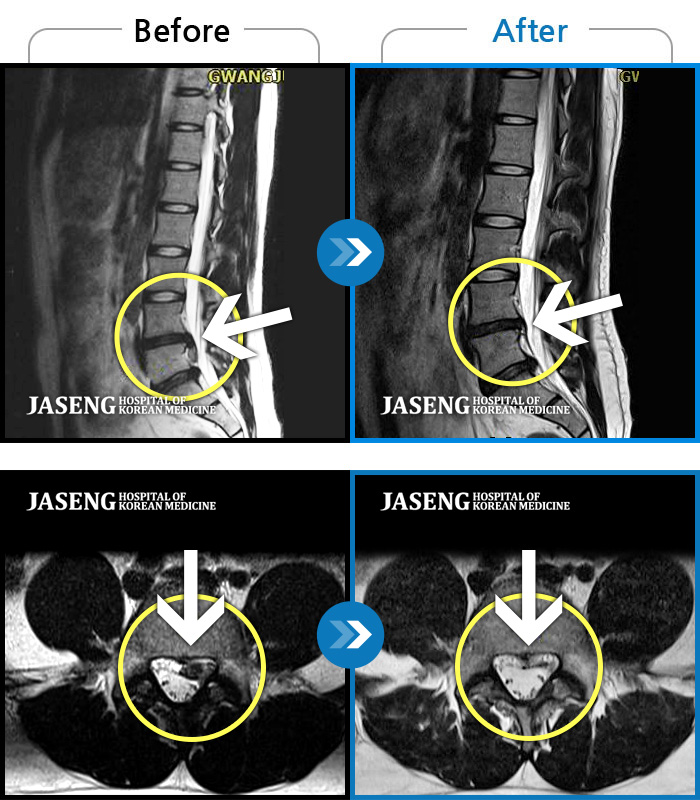

MRI 치료사례

좌측 허리부터 골반 통증, 좌측 다리 감각 저하 증상으로 내원하셨습니다.